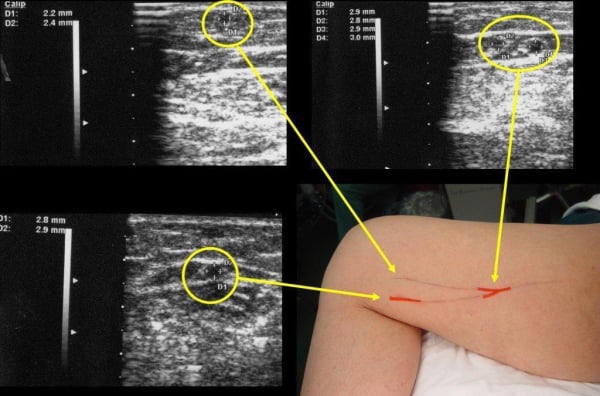

Έγχρωμο Υπερηχογράφημα Αγγείων (Colored Ultrasound Duplex Scan)

Το Έγχρωμο Υπερηχογράφημα Αγγείων, επίσης γνωστό ως Colored Ultrasound Duplex Scan, είναι μια εξέταση που συνδυάζει δύο τεχνικές υπερήχων για τον έλεγχο των αγγείων: τη δοπλερογραφία και την αντιδραστική (duplex) υπερηχογραφία. Αυτή η εξέταση παρέχει λεπτομερείς εικόνες της ανατομίας των αγγείων και πληροφορίες σχετικά με τη ροή του αίματος μέσα σε αυτά.

Η δοπλερογραφία χρησιμοποιεί ήχο κύματα για να αξιολογήσει την ταχύτητα της ροής του αίματος σε ένα αγγείο. Αυτή η τεχνική είναι χρήσιμη για τον εντοπισμό στενώσεων ή αποφραγμάτων στις αρτηρίες και τις φλέβες. Τα χρώματα στην εικόνα αντιπροσωπεύουν την κατεύθυνση και την ταχύτητα της ροής.

Η αντιδραστική υπερηχογραφία (duplex ultrasound) παρέχει δομικές εικόνες των αγγείων, όπως οι εικόνες που λαμβάνονται με την κανονική υπερηχογραφία. Σε συνδυασμό με τη δοπλερογραφία, είναι δυνατό να διακριθούν οι αρτηρίες από τις φλέβες και να αξιολογηθεί η ροή του αίματος.

Αυτή η μέθοδος χρησιμοποιείται ευρέως για την αξιολόγηση της κατάστασης των αγγείων, συμπεριλαμβανομένων των αρτηριών και των φλεβών, και μπορεί να χρησιμοποιηθεί σε διάφορα μέρη του σώματος, όπως τα άνω και κάτω άκρα, ο λαιμός, ο κορμός, και άλλες περιοχές.